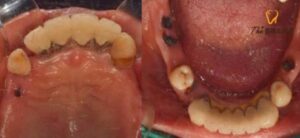

전치부와 하악 소구치 2개만 잔존해 있고

나머지 치아는 상실되거나

치근만 남아있는 상태였습니다.

하악에는 좌측 소구치를 제외한

나머지 치아는 다행히 치조골의 상태가 양호하고

치아를 보존하여 사용해도 괜찮을 것 같아서

브릿지로 연결하여 사용하기로 하였습니다.

먼저 하악의 잔존 치근들과

좌측 소구치 하나를 발치한 후

임플란트 식립을 진행하였으며,

치조골의 양이 부족한 부분에는 픽스쳐가

단단히 고정될 수 있도록

치조골 이식을 함께 진행하여

4개의 임플란트를 식립하였습니다.

임플란트 식립 후 상악에도

잔존 치아들과 치근을 모두 발치하고 난 후

본 틀니가 들어가기 전 임시 틀니를 제작해 드렸고,

잇몸이 어느 정도 아물고 난 후

틀니 제작을 시작하였습니다.